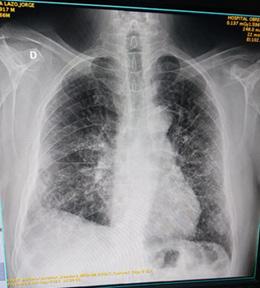

Paciente COVID-19 con trombosis e infarto agudo de miocardio

Reporte de Caso Clínico

COVID-19 patient with thrombosis and acute myocardial infarction

Rommer Alex Ortega Martínez

Gabriela Vaca Mendoza